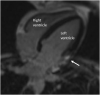

Atherosclerotic Coronary Artery Disease in a Younger Adult With Transseptal Anomalous Left Coronary Artery

We present a case of extensive coronary atherosclerotic disease in a younger patient with an anomalous left coronary artery with transseptal course and show the utility of multimodality evaluation to determine the culprit lesion in patients presenting with this rare association. (Level of Difficulty: Intermediate.).